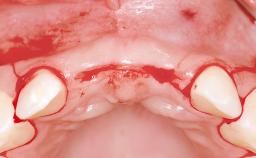

A 38-year-old woman presented with an esthetically unacceptable fixed partial denture replacing teeth 11, 21, 22. She had lost these teeth due to trauma when she was a child. The patient was not in pain but very concerned based on her previous experience that dental treatments had never satisfied her esthetic expectations. She was in good general health and reported no regular medications. No periodontal disease was noted despite the fact that the buccal flange of the prosthesis impeded cleaning of the tooth abutments. The patient did not smoke and complied with home maintenance requirements, as evidenced by her good oral hygiene status.

Bone Volume | Deficient horizontally, requiring prior grafting |

Soft Tissue Contour and Volume | Significantly deficient |